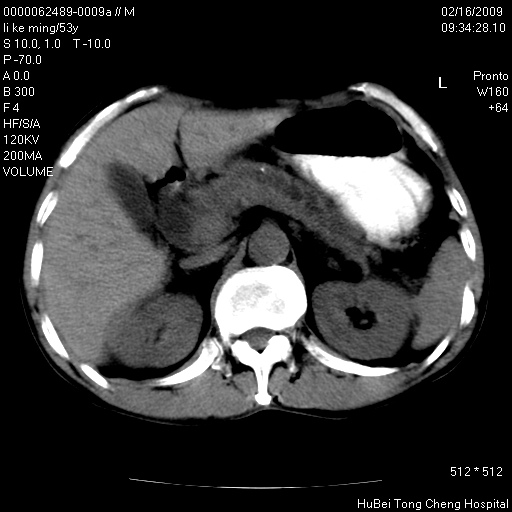

以下是引用卜一在2009-2-16 16:13:00的发言:[br]胰胆管扩张,末端明显狭窄 梗阻,胰头及十二指降段壶腹部结构紊乱。多考虑:十二指降段壶腹部癌!

以下是引用zsl6918在2009-2-17 8:48:00的发言:[br]符合胰头癌侵犯十二指肠。